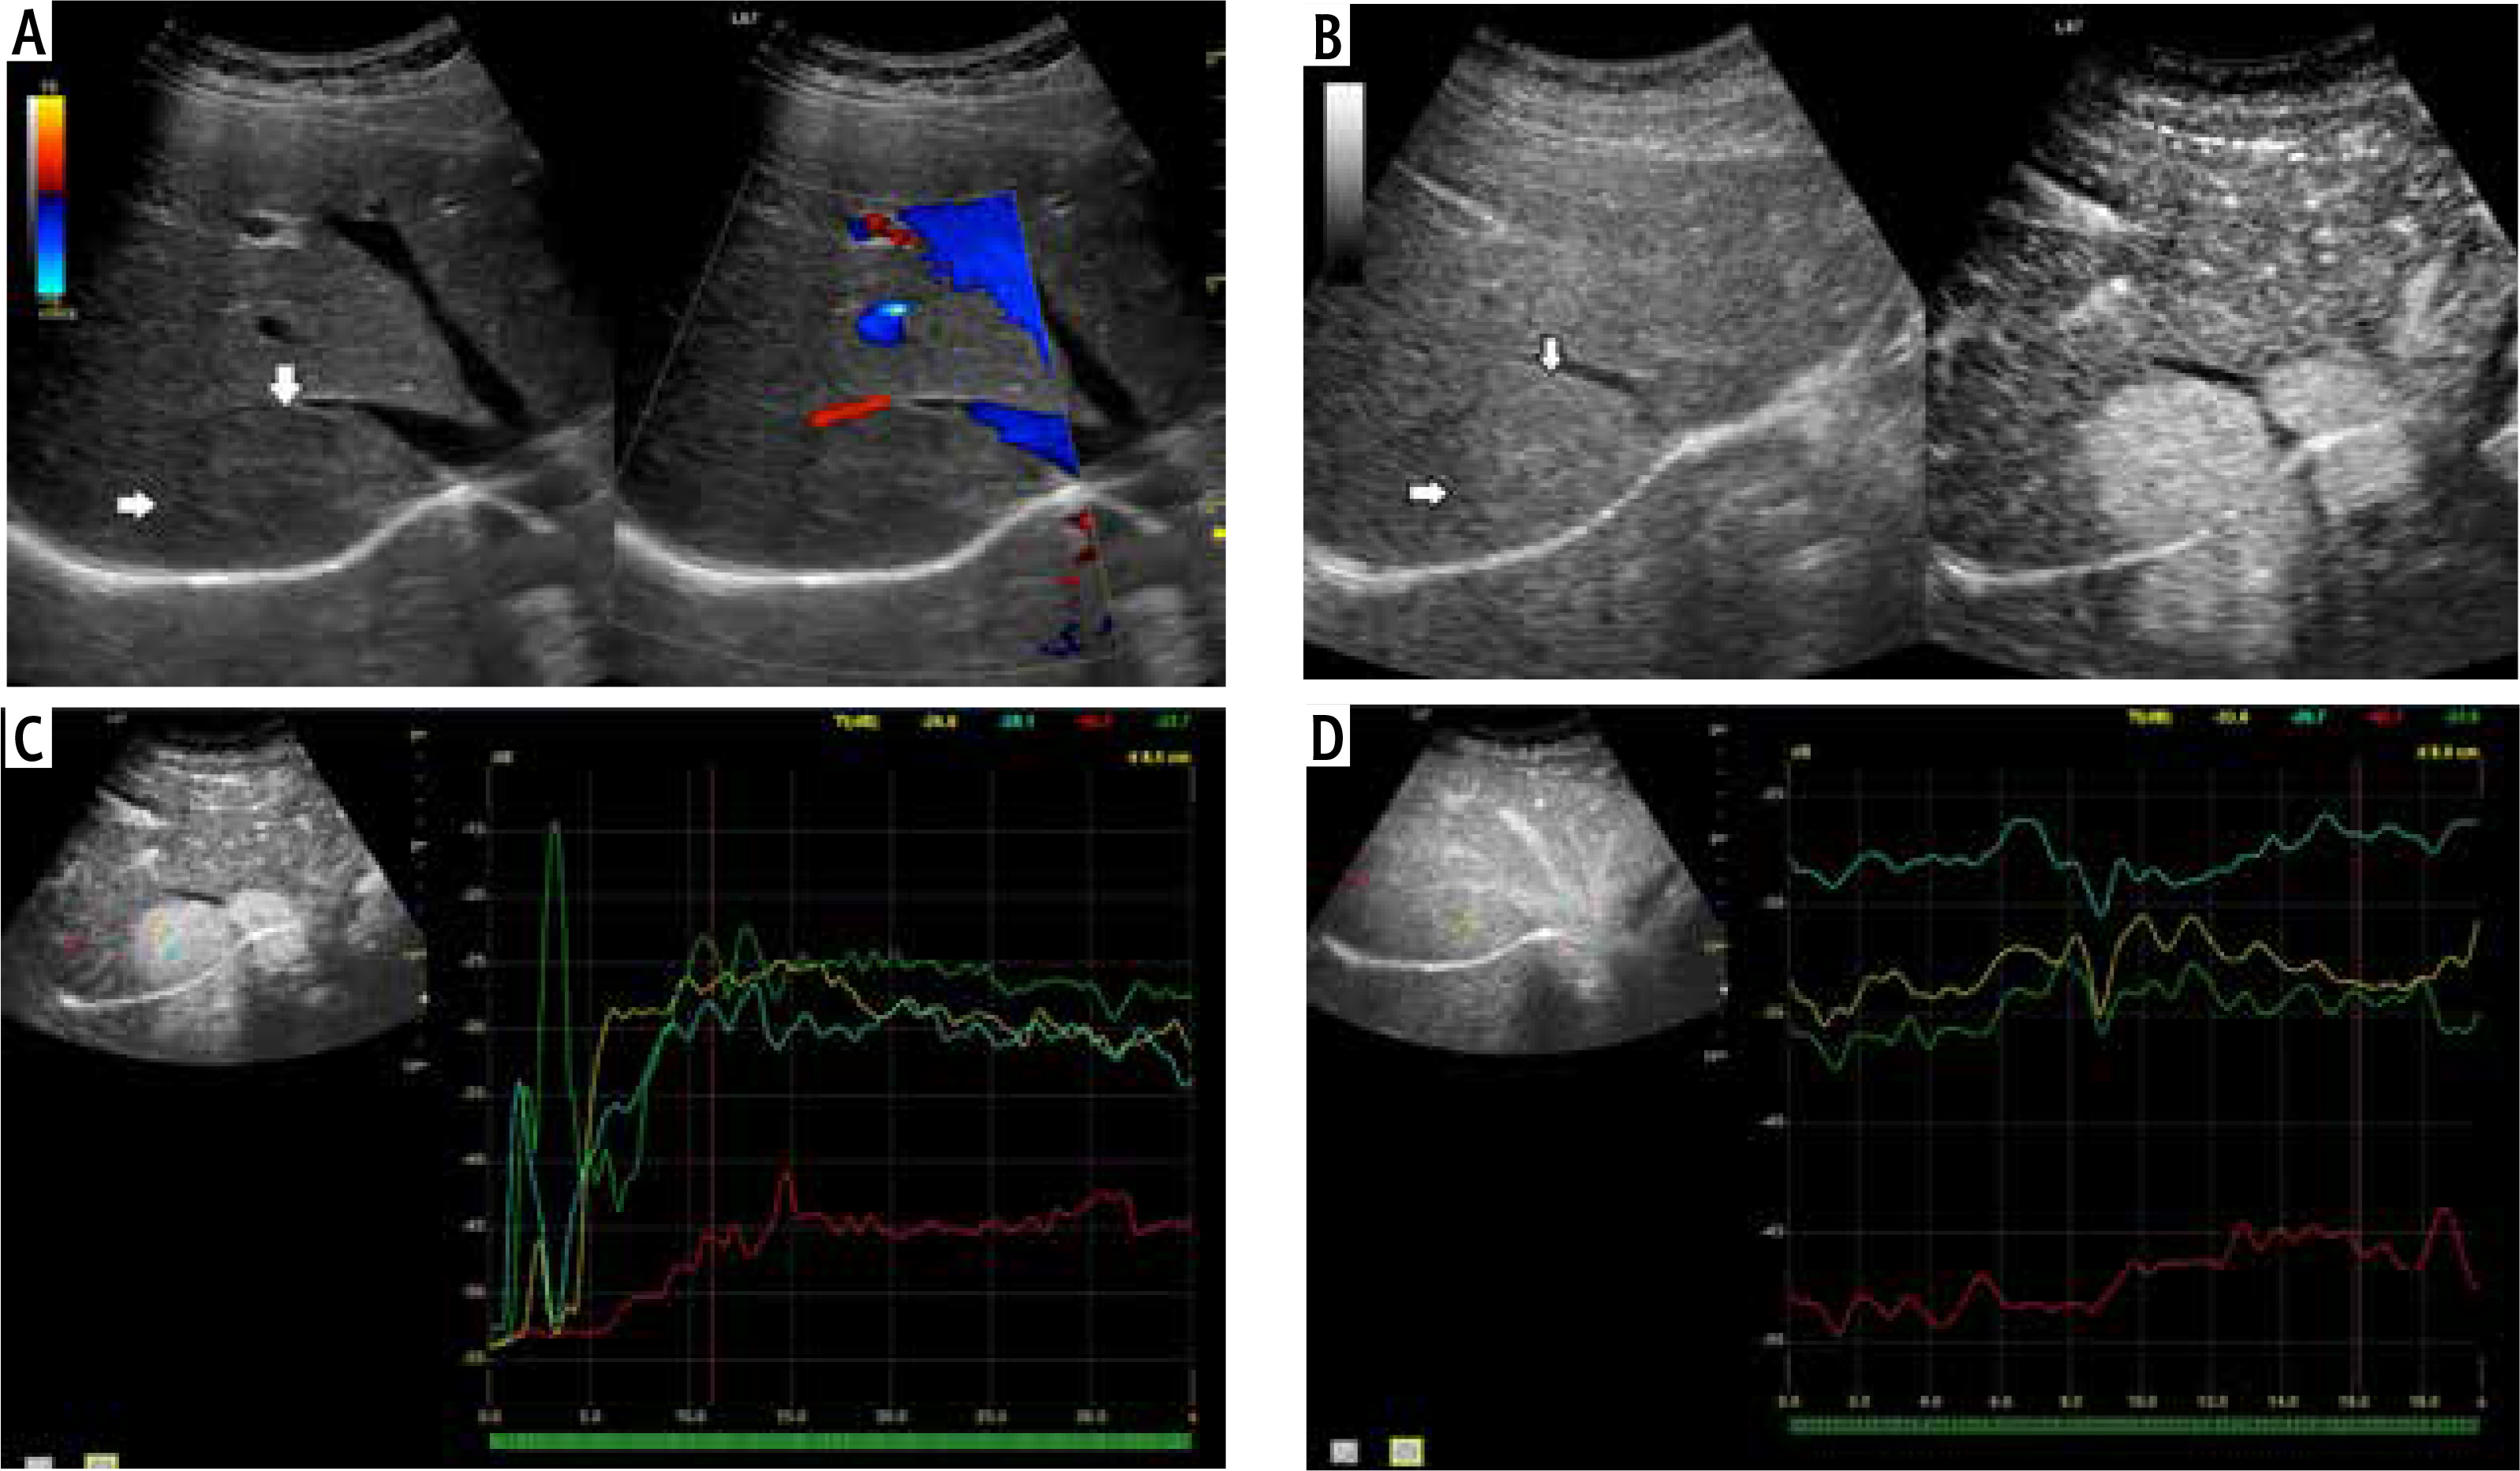

Fig. 6

A) Image of ultrasound and color Doppler in the transverse plane, focal lesion in the right lobe of the liver identified in MRI as FNH (full white arrows). Echogenicity of the lesion is slightly higher in relation to the liver parenchyma. In the central part, a small scar (an empty white arrow) is more clearly visible in the color Doppler option. B) Image of CEUS in the transverse plane of the lesion identified in MR as FNH (full white arrows). Enhancement in the early phase is higher in relation to the liver parenchyma. In the central part, the area containing the vessels, corresponding to the central fibrous scar. C) Image of CEUS. Enhancement curves in the early phase of examination. The tumor area – yellow and blue lines, with slightly delayed enhancement appears in the portal system – red line. Weaker and delayed enhancement of the liver parenchyma – the green line. D) Image of CEUS. Curves of enhancement in late phase of examination align. Area of tumor – blue and red lines, slightly stronger enhancement portal vein – yellow line. Slightly weaker enhancement of the liver parenchyma – the green line